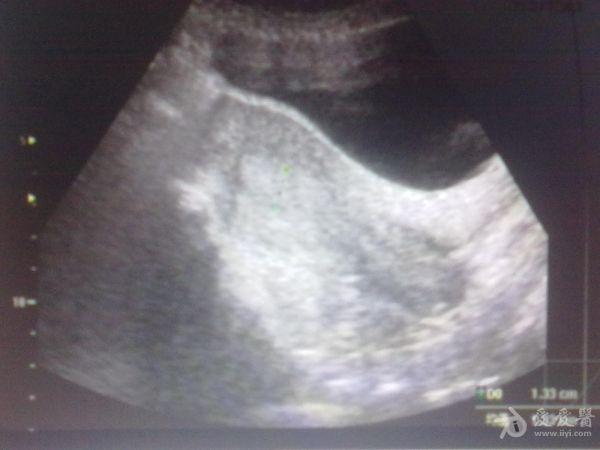

左侧卵巢囊肿?

39岁女性继发性

不孕

,月经第12天

超声

检查:左侧附件区见大小约3.6x2.7cm类圆形无回声,边界清,内透声好,右侧卵巢建多个大小不等极不规则囊泡回声,最大约1.2x1.4cm。这几幅图探头标记都在患者的右侧,也就是标记冲向我。,,显示器上的M标记在显示器的左上方。囊肿是在左侧卵巢吗?